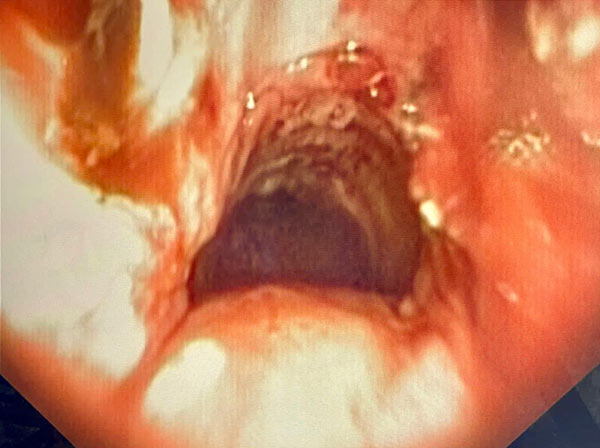

Imagens endoscópicas de Ressecção por laser de estenose traqueal, a primeira ressecando e a segunda aspecto final, com a luz traqueal totalmente aberta.